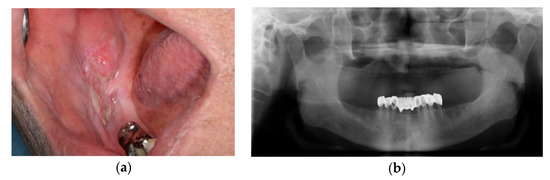

2.1. Case 1: SCC on Right Mandibular Buccal Mucosa

2.1.1. Computer-Assisted Surgical Planning

2.1.2. Surgical Technique